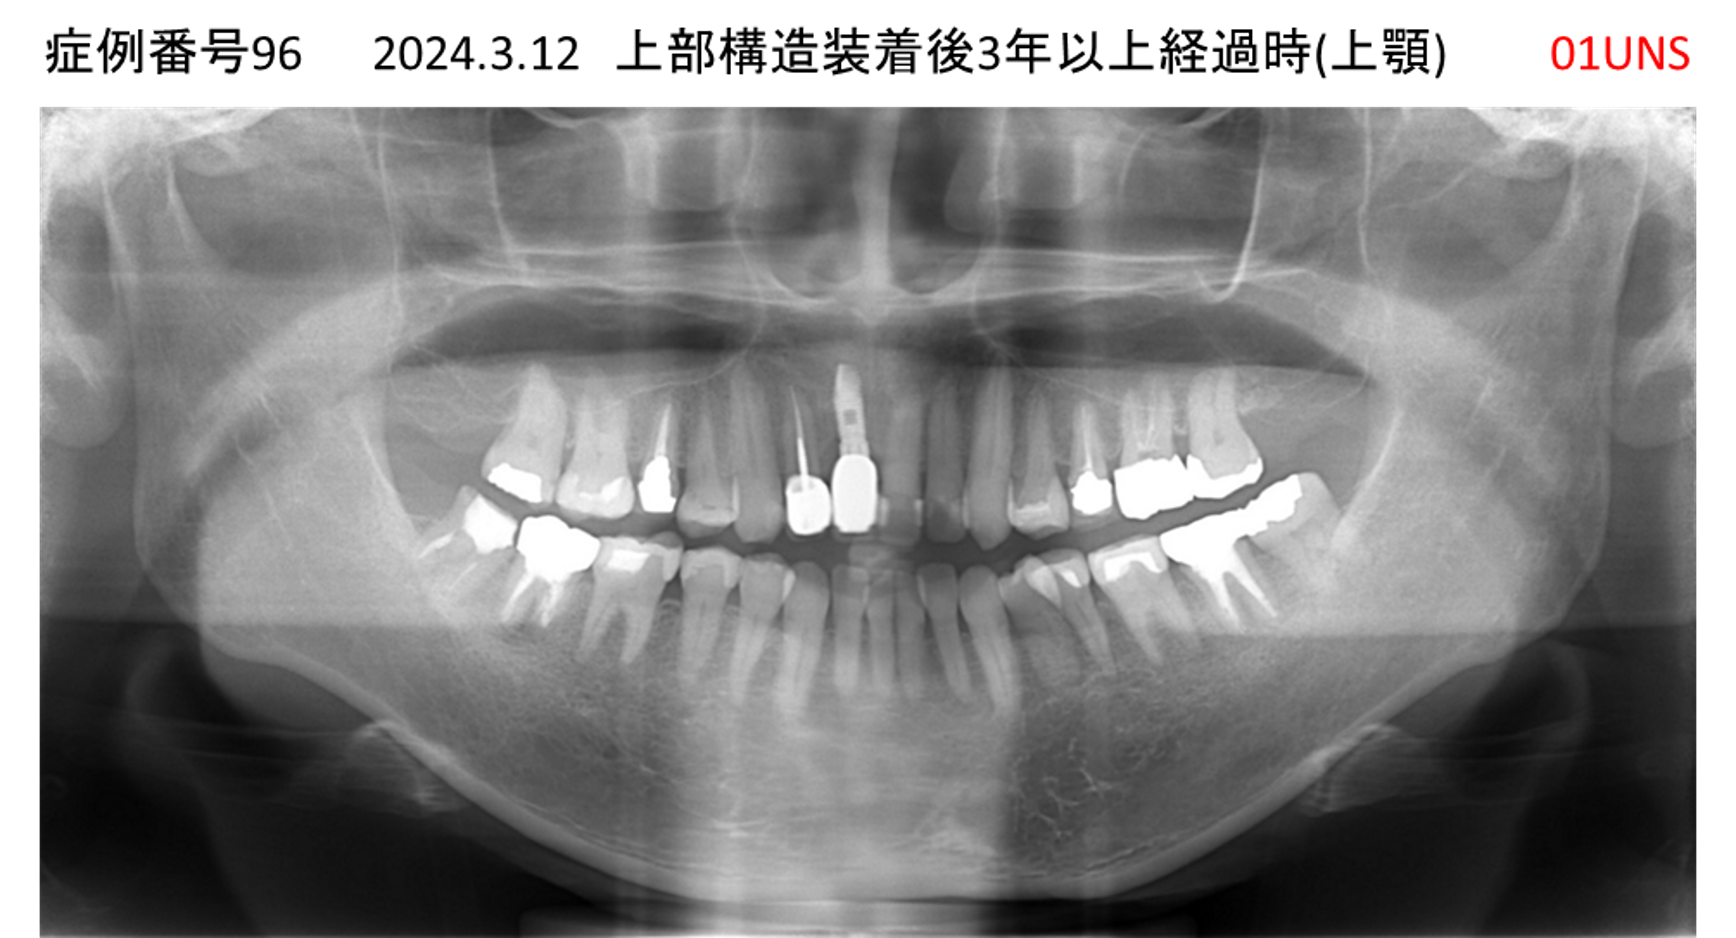

上の前歯が揺れてきてかめない患者様のインプラント症例

| 治療名称 |

インプラント |

| 治療費用 |

440万円+税 |

| 治療期間 |

6か月 |

| 患者さんの症状(主訴) |

上の前歯が揺れてきた。かめない |

| 治療内容 |

サイナスリフト、GBR、インプラント、即時荷重 |

| 治療結果 |

上の前歯の揺れが収まった。奥歯でしっかり噛める。 |

| 治療の注意点(リスク/副作用) |

インプラントが壊れたら再治療が必要 |